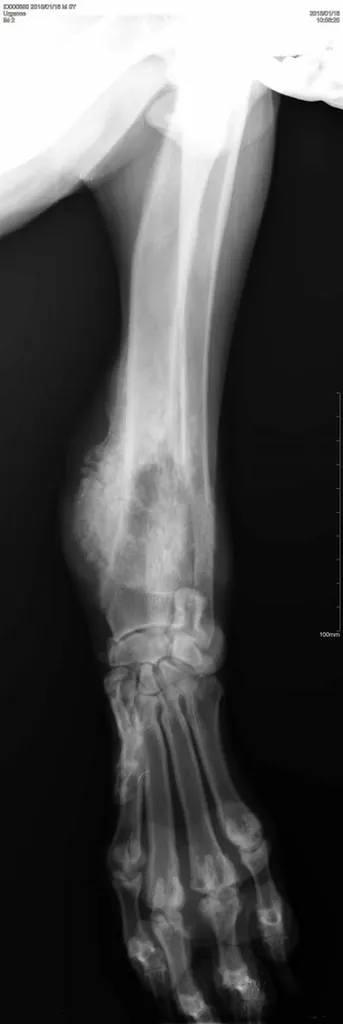

Une radiographie est un examen d’imagerie consistant à la prise de cliché au moyen d’un appareil à rayon X ceci afin de visualiser les différentes structures internes.

La radiographie reste indiquée dans de nombreuses affections, quelles soient respiratoires (radiographie cervicale ou thoracique), digestives (radiographie thoracique ou abdominale), locomotrices (membres, colonne), dentaires.

Votre chien, chat Nac est déposé sur la table de radiologie et différents clichés sont effectués dans différentes positions suivant la pathologie présentée.

Comme tout examen, il présente ses limites. Le principe de la radiographie étant l’utilisation du contraste (visualisation d’un tissu par rapport au tissu environnant et par rapport à sa radiodensité), certaines pathologies ne peuvent être que suspectées par radiographie mais nécessite d’autres examens (échographie, endoscopie, scanner, IRM).